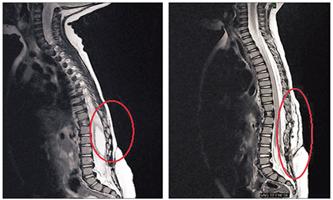

جراحة ناجحة لاستئصال كيس بالنخاع الشوكي لرضيع